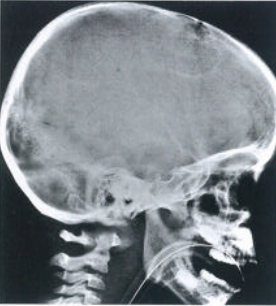

上颈椎是指位于枕骨和C2/3节段之间的结构,上颈椎损伤约占颈椎损伤的1/3。上颈椎包括枕骨髁、寰椎、枢椎椎体和其间的韧带、椎间盘等软组织。下颈椎、胸椎和腰椎因结构类似可进行统一分类,而上颈椎各个节段结构各不相同,需分别进行分类。

枢椎骨折

枢椎有两种典型的骨折,齿状突骨折和外伤型枢椎滑脱(Hangman骨折或绞刑骨折)。C2/3间的骨折详见下颈椎的骨折分类。

齿状突骨折Anderson和D' Alonzo将齿状突骨折分为3型(图14):Ⅰ型:齿状突尖骨折齿状突尖的斜形骨折,受伤机制可能为剪切外力导致齿状突尖撞击枕骨大孔边缘,也见于寰枕关节脱位时的翼状韧带撕脱骨折。Ⅱ型:齿状突骨折骨折线位于齿状突基底,C2椎体上方。骨折接触面小,保守治疗容易出现骨折不愈合。骨折线也可为斜形,此时齿状突可向前或向后移位。Ⅲ型:经枢椎体的齿状突骨折骨折线位于枢椎椎体,齿状突腰部以下。Anderson和D' Alonzo报道此型骨折线位于松质骨内,容易愈合,保守治疗的不愈合率仅为7%。骨折线常进入侧方寰枢关节并导致关节面台阶。

图14 Anderson和D' Alonzo齿状突骨折分类